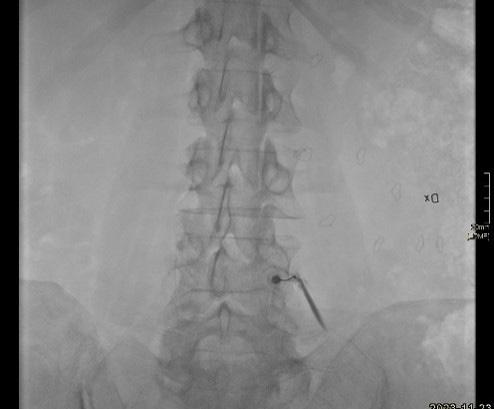

Bild 1. En okänd sklerotisk förändring dorsala kaudala omfånget av kotkroppen som punkteras av en benbiopsi nål under DT-vägledning. Bild 2. En intrakortikal hypodens förändring med sklerotiskt nidus och utseende som osteoid-osteom. En radiofrekvensablation utfördes i centrala nidus av förändringen. Uppföljande undersökningar visade god effekt utan recidiv. Bild 3. Patient med kronisk tendinos i Achilklessenan med kärlinväxt i den spolformiga senan. Injektion av aethoxysklerol för att sklerosera patologiska kärlkluster. Bild 4. Nervrotsblockad i L4. Kontrastinjektion visar att nålen ligger på rätt plats i nervskidan där den utgår från spinalkanalen. Mepivacaine och Depo-Medrol injicerades för smärtlindring och långvarig inflammationsdämpning.